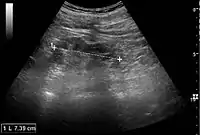

Acute pyelonephritis with increased cortical echogenicity and blurred delineation of the upper pole.[16]

Ultrasound findings that indicate pyelonephritis are enlargement of the kidney, edema in the renal sinus or parenchyma, bleeding, loss of corticomedullary differentiation, abscess formation, or an areas of poor blood flow on doppler ultrasound.[21] However, ultrasound findings are seen in only 20% to 24% of people with pyelonephritis.[21]

Chronic pyelonephritis with reduced kidney size and focal cortical thinning. Measurement of kidney length on the US image is illustrated by ‘+’ and a dashed line.[16]